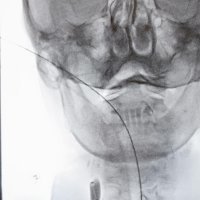

Sam zahvat odvija se otprilike na sljedeći način: nakon što pacijent prođe hitni prijam, neurologa te hitni CT i angiografiju koja pokazuje u kojem dijelu mozga je tromb, bolesniku se kroz arteriju u preponi uvodi dugački kateter, sve do mjesta u mozgu gdje se smjestio tromb. Kroz njega potom prolazi manji mikrokateter kojom se provodi takozvani stent retriever. Kad se oslobodi, on se u sljedećih nekoliko minuta raširi u mrežicu kojom se lovi krvni ugrušak.

Krvna žila potom se zatvori balonom kako krv ne bi otplavila tromb, a stent se povlači u kateter, zajedno s trombom. Postupak se ponavlja sve dok se i posljednji komadić tromba ne izvadi iz krvne žile. Druga metoda uključuje nadovezivanje katetera za aspiraciju. Ona se spaja na crpku koja usisava tromb. Izbor metode ovisi o veličini krvnog ugruška i mjestu na kojem se nalazi.